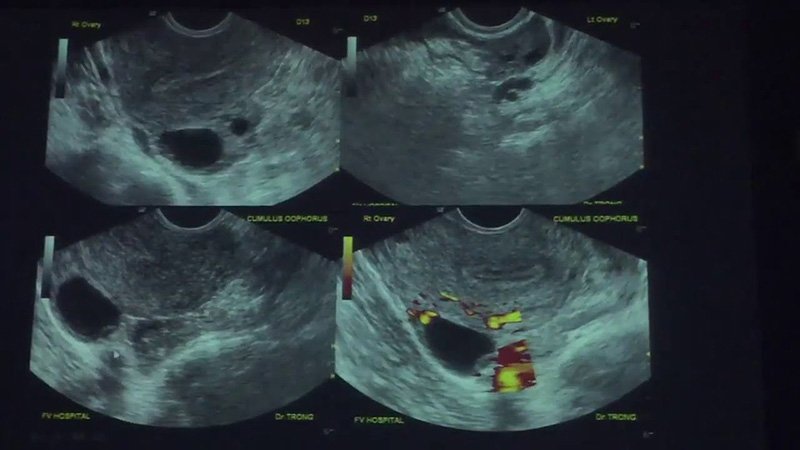

2. Kích Thích Buồng Trứng và Theo Dõi Nang Trứng

Tiêm thuốc kích trứng

Trong giai đoạn này, bác sĩ sẽ chỉ định tiêm thuốc để kích thích sự phát triển của các nang trứng.

- Thuốc được tiêm hàng ngày trong khoảng 8-14 ngày.

- Theo dõi bằng siêu âm để đánh giá sự phát triển của nang trứng và điều chỉnh liều lượng nếu cần.